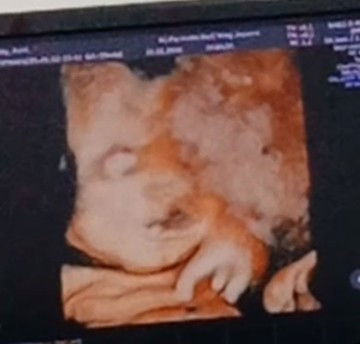

Hasil USG 33 week Kenapa bibirnya kaya ada yang aneh ya ?

Mohon penjelasannya bunda buat yang sudah pengalaman dan faham .. Dari kemaren parno sendiri liat hasil nya kaya bibir nya aneh .... Kira2 kenapa ya bunda apakah normal apakah ada kelainan?? #mohonbantujawabbunda #Sharingdong_Bund #bantujawab #sharing